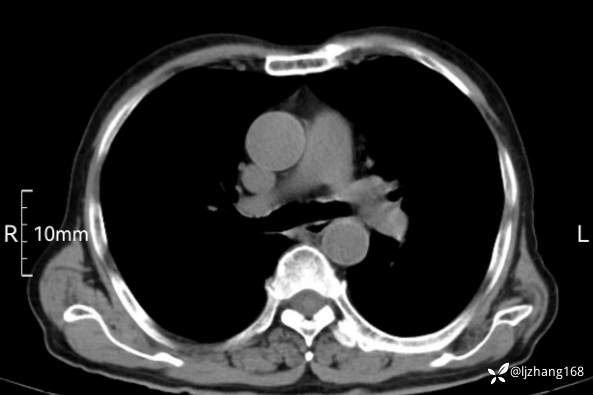

辅助检查:胸部CT:双肺肺气肿,间质性病变,血气分析:PH 7.413, PCO2 29.2mmHg, PO2,81.8mmHg,乳酸 3.3mmol/1,剩余碱-4.0mmol/1,HC03 18.8mmol/1。全血超敏C反应蛋白:超敏C反应蛋白 135.60 mg/L、 白细胞 14x19^9/L,中性粒细胞11.6x10^9/L。